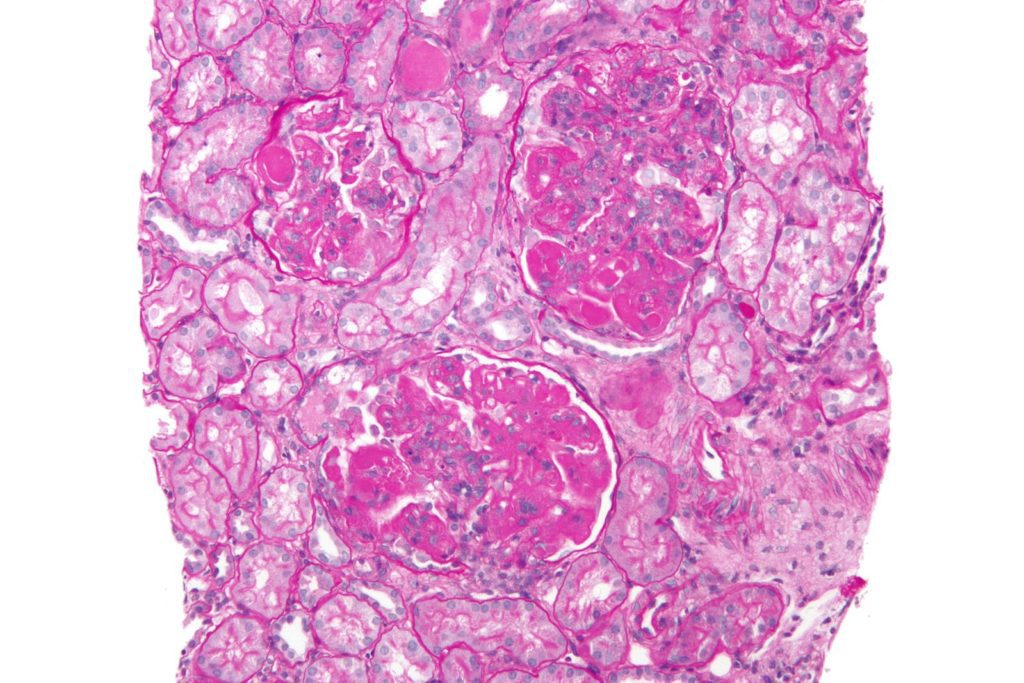

[0]Image credit: https://commons.wikimedia.org/wiki/File:Diffuse_proliferative_lupus_nephritis_-_high_mag.jpg

Lupus is also known as systemic lupus erythematosus (SLE) and it is the condition in which the immune system attacks the cells of the body causing widespread inflammation in multiple organ systems.

Symptoms are variable but often include painful joints and extreme tiredness. There is often a butterfly-shaped red rash that develops on the person’s face. This rash usually is found over the nose and extending onto the cheeks. Ulcers often occur in the mouth on the mucous membranes between the palates and lymph nodes throughout the body may become swollen and enlarged. Other symptoms may occur depending on which organs are affected and may include, for example, kidney inflammation, pleurisy, anemia, and gastrointestinal problems.

The diagnosis can be difficult because the disease may resemble other conditions. However, physicians can use a range of tests including a complete white blood cell count, recognition of the symptoms, particularly the butterfly rash, and various antibody tests. A good indication that someone may have lupus is the presence of antinuclear autoantibodies. Furthermore, higher than usual levels of anti-dsDNA antibodies are indicative of a person having lupus.

Treatment can include the use of non-steroidal anti-inflammatory medicines to help with joint pain in cases where the disease is not too severe. In more extreme cases the patient can be treated with corticosteroid therapy in order to reduce the immune response. In very severe cases patients may need a kidney transplant if the kidney is too badly damaged by the disease.

It is not known for certain what causes lupus to occur but it is thought to be due to a combination of both genetics and environmental factors. In fact, scientists have found an association between several genetic mutations and the development of lupus. Groups with the highest risk factor include women of child-bearing age (between the ages of 16 and about 45), and who are of non-Caucasian race.